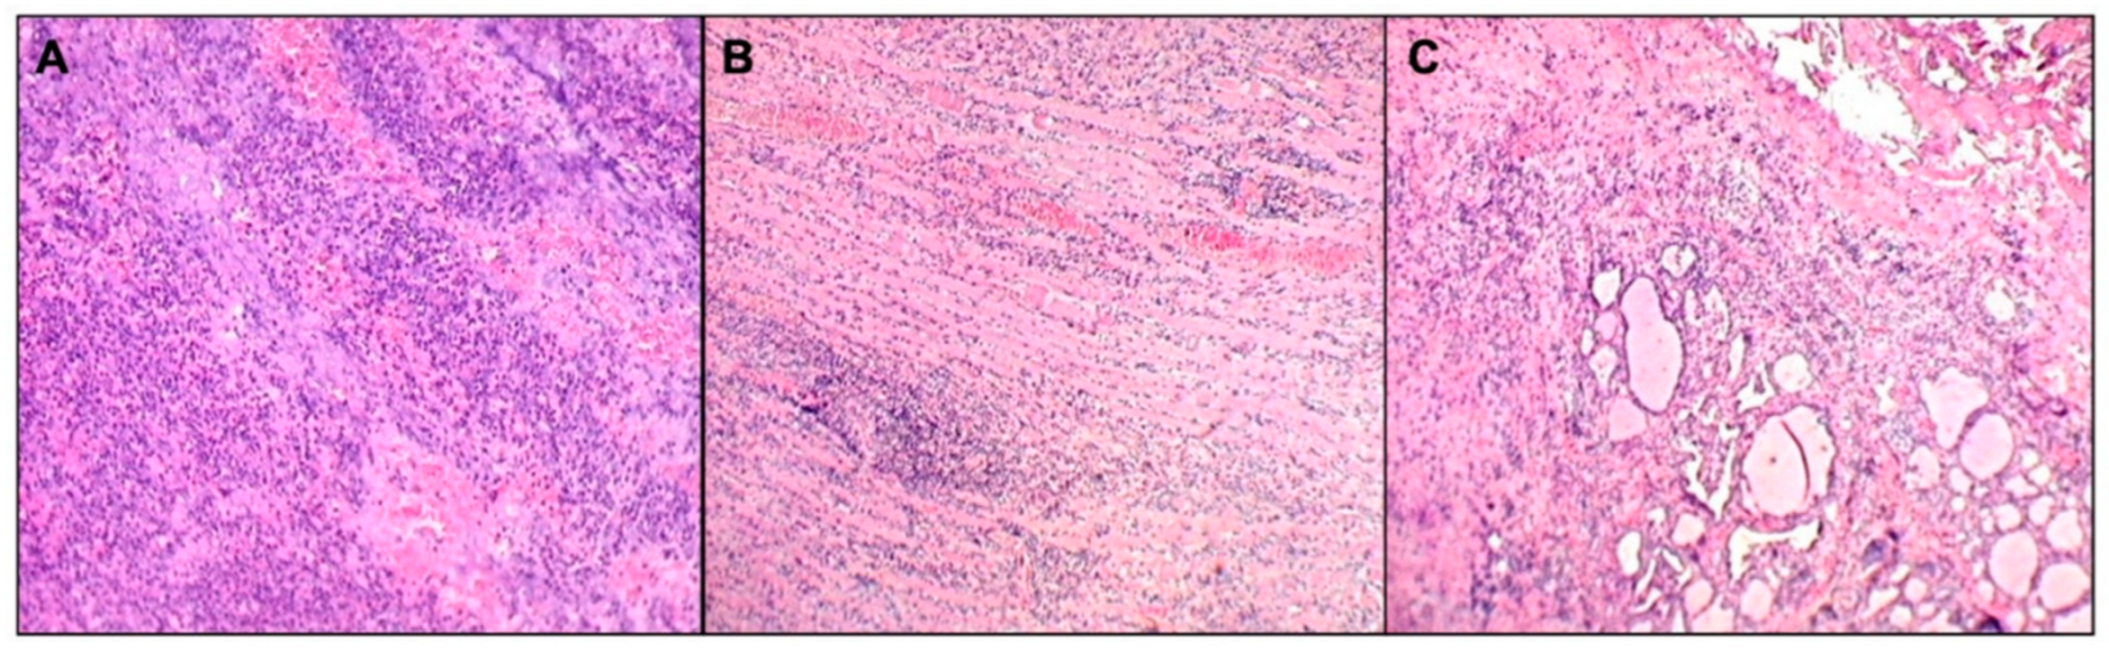

2.2. Investigations for Recurrent Neck Abscesses